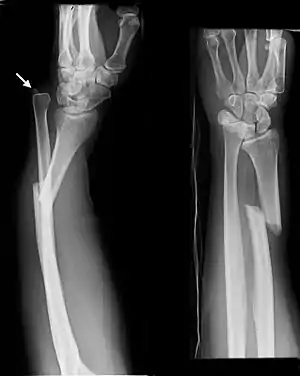

The dislocation of ulnar head in Galeazzi fracture dislocation may be dorsal (commoner) or volar (rare) depending on the mechanism of injury. If the fall is on the outstretched hand with forearm in pronation, the dislocation is dorsal, and if forearm is in supination at the time of injury, the dislocation is volar.[2]

Galeazzi fractures account for 3-7% of all forearm fractures. They are seen most often in males. Although Galeazzi fracture patterns are reportedly uncommon, they are estimated to account for 7% of all forearm fractures in adults.[1] They are associated with a fall on an outstretched arm.